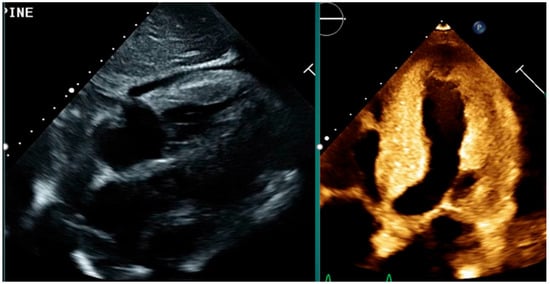

Multimodality Imaging in Cardiac Amyloidosis

by Mayuresh Chaudhari and Mahi Lakshmi Ashwath

Cardiac amyloidosis is an underdiagnosed cause of heart failure characterized by extracellular deposition of misfolded proteins. Advances in non-invasive imaging, including echocardiography, cardiac magnetic resonance imaging (CMR), and radionuclide imaging, have significantly enhanced the diagnostic accuracy and monitoring of cardiac amyloidosis. This review [...] Read more.

Cardiac amyloidosis is an underdiagnosed cause of heart failure characterized by extracellular deposition of misfolded proteins. Advances in non-invasive imaging, including echocardiography, cardiac magnetic resonance imaging (CMR), and radionuclide imaging, have significantly enhanced the diagnostic accuracy and monitoring of cardiac amyloidosis. This review explores the role of each modality, their individual strengths, and current consensus recommendations. Emphasis is placed on the integration of multimodal imaging to guide diagnosis, prognosis, and therapeutic decisions in both AL and ATTR amyloidosis. Full article

Show Figures

Figure 1